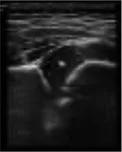

In this study, the weights of each anatomical structure obtained by entropy weight method were respectively bony rim point: 0.29, lower iliac limb point: 0.41, glenoid labrum: 0.30. That means the last weighted score of ultrasound image quality = bony rim point × 0.29 + lower iliac limb point × 0.41 + glenoid labrum × 0.30 (Figure 4). And the proportion of the final weighted score of ultrasound image lower than 3 in each month were 16%, 20%, 14%, 14%, 33%, 27%, 43%.

FIGURE 4

www.frontiersin.org

Figure 4. (A) The image structure of the 5-month-old subject was not clearly displayed, scoring only 2.30. (B) In contrast, the 8-month-old subjects had a clearly displayed image structure, achieving a score of 4.01.